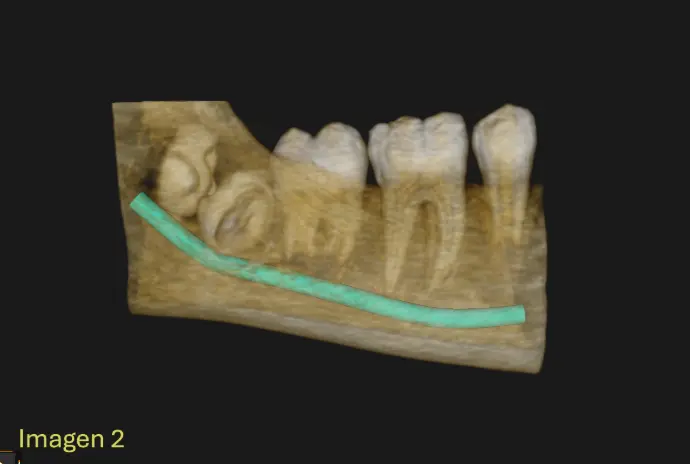

​Se Observa en la Cone Beam la formación dentro de un mismo saco coronario la formación de dos estructuras coronarias, correspondiendo a Pd 48 y Pd 49 (4to molar) Ambas piezas en proceso de formcion, completamente incluida, en intimo contacto con el conducto dentario inferior derecho sin signos de desplazamientos evidentes (IMG. 2), Ambas piezas dentarias se encuentran incluidas con la corona enfrentadas (IMG. 3),